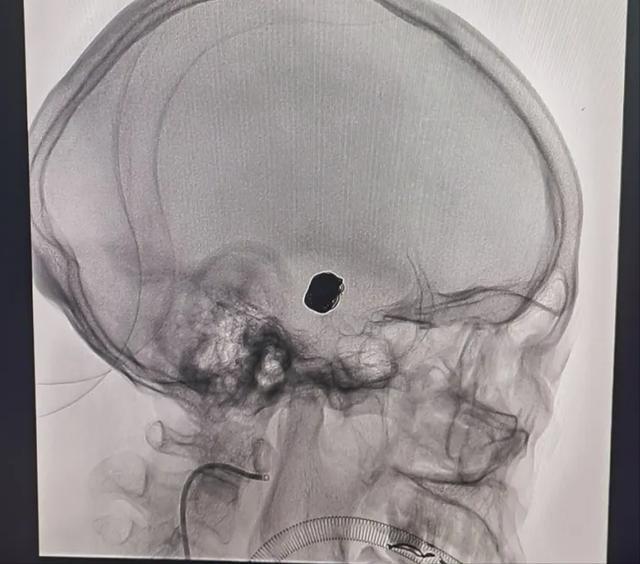

术中,脑血管造影发现患者右侧颈动脉交通段有一大小约13.58*11.64mm动脉瘤(如蚕豆大小)。

在影像引导下,主刀医师冯铁桥教授通过微导管分别在动脉瘤中填入大小不等14个弹簧圈,造影显示动脉瘤被堵塞致密,脑动脉血液通畅。患者术中、术后神志镇静,状态平稳,无明显不适,安返病房。

(▲术后头颅影像)